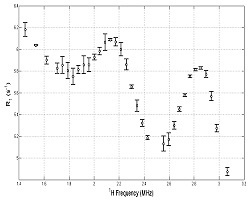

Field-cycling inversion-recovery pulse sequence using PRESS localisation. Spins are inverted using the AFP pulse, then relaxation occurs at field B0E, followed by selective excitation and echo formation. The sequence is repeated at a range of B0E values to build up a T1 dispersion curve. In order to measure a localised T1 dispersion curve, one or more pilot images are collected, on which regions-of-interest are drawn using the mouse. These define the cuboid volume from which the NMR signals are produced. The scanner's software then calculates the necessary magnetic field gradient values (G1, G2 and G3 in the above diagram), then runs the pulse sequence to generate the data. An example of a pilot image and a resulting R1 dispersion plot (R1 = 1/T1) are shown below.

Pilot image (59 mT) through thighs of a volunteer, showing in red the region-of-interest where it intersects the image plane.

R1 dispersion curve on the right was obtained from the selected volume. The quadrupole peaks due to immobile protein within muscle can clearly be seen. - Rapid FFC-MRI